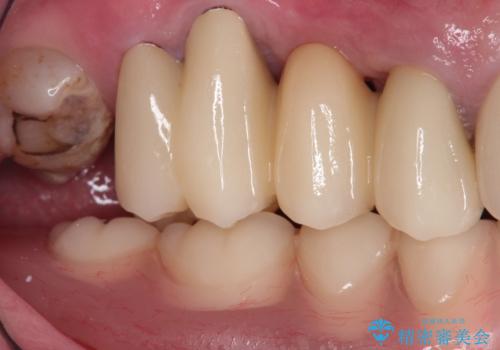

奥歯が欠損しており、上下の前歯が強く咬合する可能性があったので、上顎前歯の裏側は金属のものにしました。

お忙しい方でしたので、治療が終了するまでにじかんがかかってしまいましたが、奥歯でもしっかり咬めるようになったと喜んでいただけました。